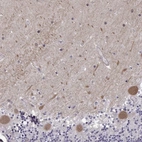

Immunohistochemical staining of human cerebellum shows moderate cytoplasmic positivity in Purkinje cells.